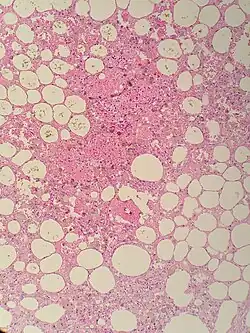

| Sclerosing mesenteritis - note the hemosiderin, chronic inflammation | |

The disorder is identified by histopathology showing fat necrosis, fibrosis and chronic inflammation of the small intestine. Examination of the mesentery may indicate a solitary mass, but diffuse mesentery thickening is common.[4][6]